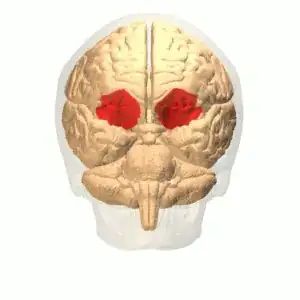

Amygdala

CG illustration of the amygdala's location

One of the main regions commonly associated with APD and antisocial behavior, and in particular with its remorselessness criterion, are the amygdala (Blair and Frith, 2000). However, while the amygdala's heavy involvement in emotional processing is well established (Kandel, 2013), and a veritable sea of studies support an emotional processing deficits and abnormalities in the amygdala for general antisocial behavior (e.g., Coccaro et al., 2006; Narayan et al., 2007; Veit et al., 2002) over different antisocial disorders, I couldn't find any direct investigations of amygdaloid activity in APD patients.